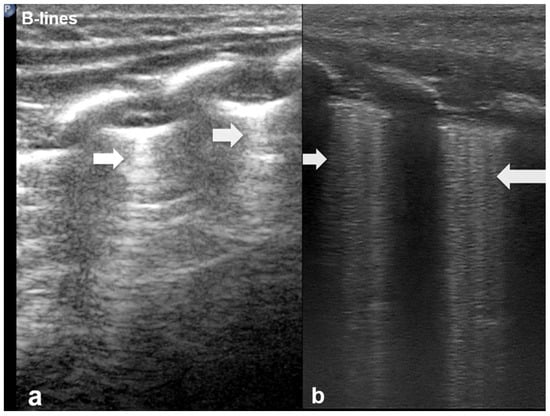

3.1.5. Sea-Shore Sign

The “sea-shore sign” is a characteristic ultrasound finding observed during M-mode (motion mode) scanning, and is indicative of normal lung sliding. In this pattern, the pleural line and overlying chest wall structures produce a series of horizontal echogenic lines, representing static tissues (Figure 6).

Figure 6.

Upper image: LUS with normal A-Lines in B (bright)-mode. The simultaneous M (motion)-mode image (lower image) reveals series of horizontal echogenic lines which represent the pleural line and its reverberations (A-lines), as well as the air-filled alveoli with a granular/sandy appearance (more prominent in real time scan). These in combination produce the seashore sign.

In contrast, the underlying lung parenchyma, which moves in synch with respiration, generates a granular or sandy appearance due to the dynamic motion of air-filled alveoli [17]. This combination creates the visual effect of waves (static layers) above and sand (with a dynamic speckled texture) below, thus producing the so-called “sea-shore sign”. The presence of this sign confirms normal apposition and movement of the visceral and parietal pleurae, and can be used to effectively rule out pneumothorax at the examination site. The “sea-shore sign” is considered to be a reliable and non-invasive indicator of intact lung sliding, and is frequently used in both adult and neonatal lung ultrasound to assess respiratory function and pleural integrity [5,6,15,22,23].

When this sign is absent, uniform horizontal straight lines, known as the stratosphere sign or “barcode sign”, appear, indicating pneumothorax as a possible cause [18,24].